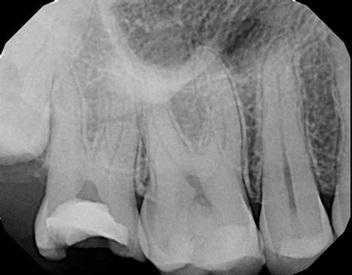

35-летний мужчина обратился за стоматологической помощью по причине сильной боли с правой стороны челюсти и лица. Он не мог самостоятельно четко определить источник боли, но ее интенсивность возрастала на протяжении последних нескольких дней. Сначала пациент чувствовал, что боль распространяется с области нижней челюсти, но за последние 24 часа боли иррадиировала и в проекцию верхней челюсти. Из-за болевых ощущений он практически не спал, а 220 мг принятого им напроксена лишь незначительно снизили интенсивность болевых ощущений. По данным анамнеза удалось установить факт реставрации зубов 2 и 30 в период последних 10 лет. В ходе клинического осмотра были верифицированы признаки микроподтекания вокруг огромной композитной реставрации на окклюзионной поверхности зуба 2. Вторичный кариес был идентифицирован на щечной стороне 30 зуба в области интерфейса соединения реставрации с твердыми тканями. Зуб 1 в ротовой полости не визуализировался. И зуб 30, и зуб 2 не реагировали на провокационные тесты, в то время как соседние зубы демонстрировали нормальную чувствительность к воздействию факторов холода и в ходе проведения электроодонтометрии. На перкуссию и пальпацию все дистальные зубы на верхней и нижней челюсти реагировали нормально, также не было обнаружено признаков отека, свищевого хода или пародонтальных дефектов. На периапикальной рентгенограмме были визуализированы признаки предварительного выполнения пульпотомии зуба 2, без наличия симптомов смежного апикального поражения (фото 5).

Фото 5. Клинический случай 2. Рентгенограмма области дистального правого квадранта верхней челюсти.

В проекции же зуба 30 на рентгенограмме были идентифицированы признаки периапикального поражения и глубоко размещенная реставрация. Таким образом, для зуба 2 был поставлен диагноз предварительно инициированного лечения без смежных периапикальных изменений, в то время как для зуба 30 был поставлен диагноз некроза пульпы и симптоматического апикального периодонтита. При этом было очевидно, что оба зуба нуждаются в проведении полного адекватного эндодонтического лечения. В ходе выполнения селективной анестезии 1,7 мл 4% раствора септокаина с концентрацией адреналина 1: 100 000 путем щечной инфильтрации в проекции зуба 2 не удалось уменьшить интенсивность болевых ощущений. Однако после этого пациент отметил, что боль начала концентрироваться в правом квадранте нижней челюсти. Дальнейшее введение 1,7 мл 2% раствора ксилокаина с концентрацией адреналина 1: 100 000 в ходе блокады нижнего альвеолярного нерва позволило полностью нивелировать болевые ощущения. Затем в зубе 30 была проведена пульпэктомия, и на следующий день пациент сообщил о разрешении всех болевых симптомов.

Фото 6. Клинический случай 2. Рентгенограмма области дистального правого квадранта нижней челюсти.